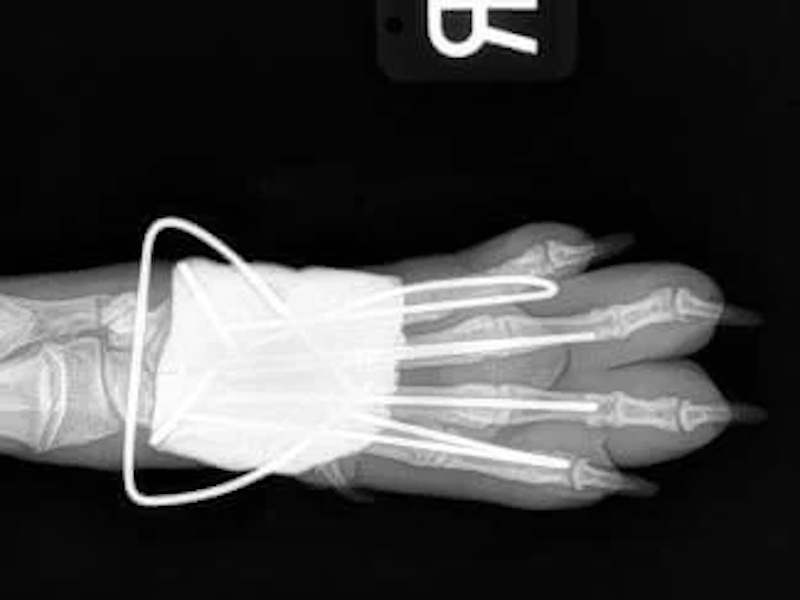

Carpal Hyperextension

- Pan-Carpal Arthrodesis: $6,500 - $8,000+

- Partial Carpal Arthrodesis: $5,250+